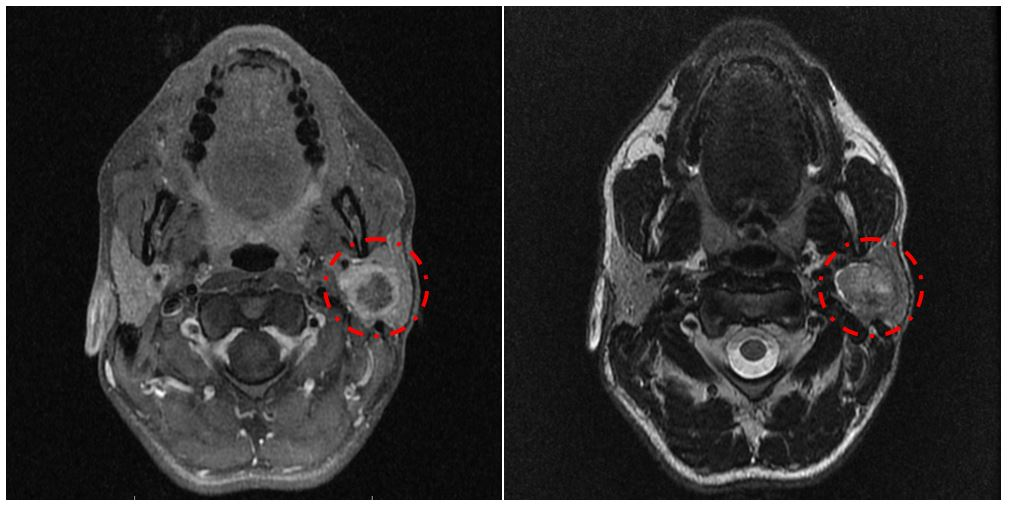

В настоящее время в связи с развитием направления хирургического лечения новообразований околоушной слюнной железы все более актуальным является ранняя диагностика посттравматической послеоперационной невропатии лицевого нерва, а также последующее своевременное и комплексное реабилитационное лечение, включая как медикаментозную, так и немедикаментозную терапию. Несмотря на современные хирургические технологии, а также применение интраоперационного нейромониторинга, избежать повреждения лицевого нерва и его ветвей при операциях на околоушной слюнной железе практически невозможно.

МРТ головного мозга пациента с признаками новообразования околоушной слюнной железы